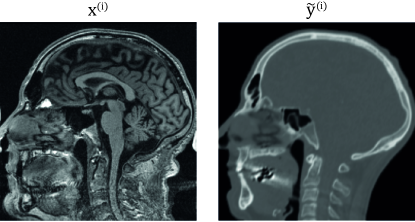

For the experiments we used CERMEP-IDB-MRXFDG data set which is freely available for research use [41]. The data set consists of 37 rigidly registered CT and T1 MRI head scan pairs. We resampled all the images to the MRI-resolution of . Pre-processing of the T1 images was similar to the one done for the cross-modality MRI synthesis data set as we applied N4 bias correction [53] using Advanced Normalization Tools (ANTs) software [5] and normalized the brain white-matter to the mean value of one using the implementation by Reinhold et al. [46] together with the implementation by Iglesias et al. [21] for brain mask extraction. We additionally removed any external objects from the CT images using series of morphological operations. While the skull and brain regions are relatively rigid, the image volumes extend to neck region with significant registration mismatches as can be seen in Figure 5. We divided the data set to cases for training, for validation, and for testing.

While close to our method metric-wise, under visual inspection the images generated by NeMAR with our components contained more easily visible alignment mistakes than the images generated by our models. Probably the easiest mistake to notice was its inaccuracy in predicting the body outline at neck region, where the data set contains the largest systematic deformation differences. An example of such a case is shown in Figure 10. More subtle mistakes included soft tissue boundaries being placed slightly off. Geometric accuracy of tissue boundaries is important as the pseudo CT images might also be used for positioning at the linear accelerator. The result is in line with the paper introducing NeMAR [1] as in the supplementary materials they conclude that their image-to-image translation network produces geometrically accurate results only when the image synthesis generator model is significantly smaller than the one used here.